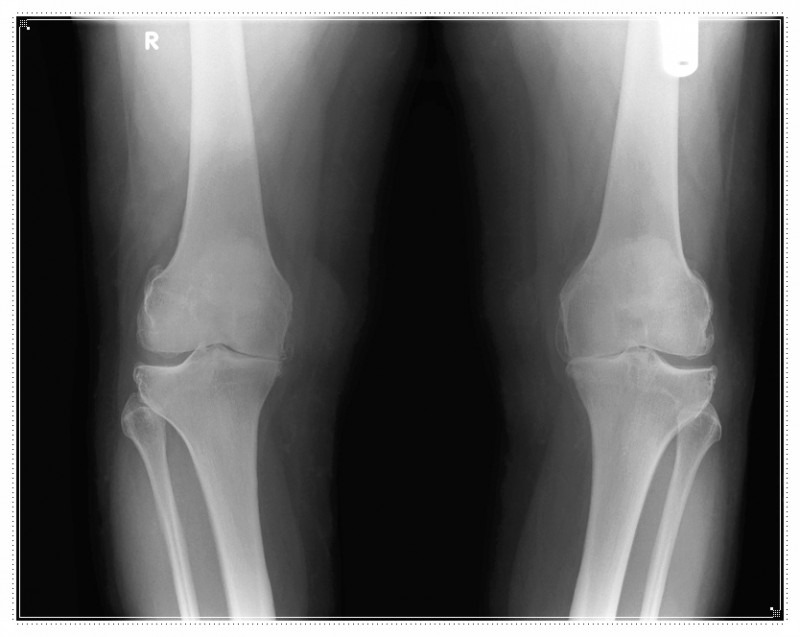

하지 정렬의 문제

다리가 바깥쪽으로 틀어지거나 체중이 한쪽으로 실리면 무릎 뒤쪽 특정 부위만 계속 압박을 받게 됩니다.

본인은 알아차리지 못하는 경우가 대부분입니다.